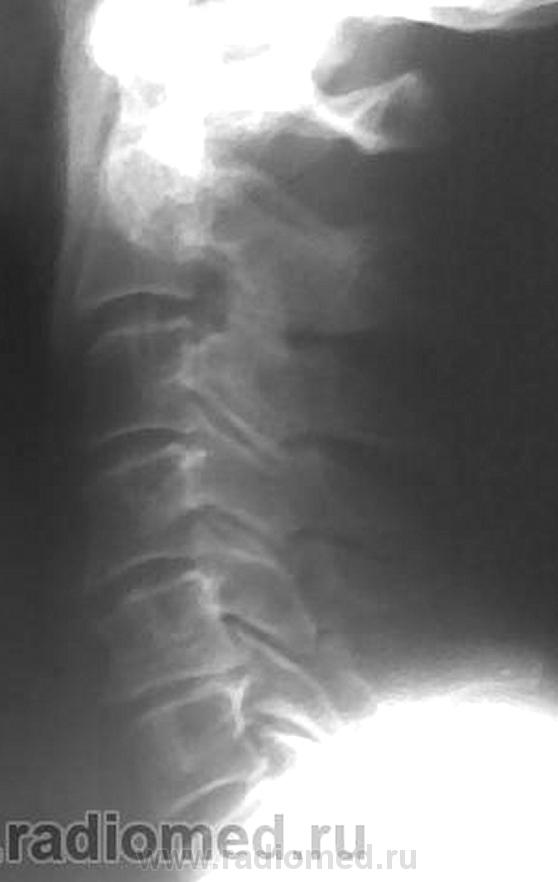

Остеохондроз, спондиллоартроз, протрузия МПД С5-С6 кзади. Что Вас смущает на этих снимках? Игра теней на уровне С6(прямой снимок)?

В теле С5 поперечное посветление в боковой, видимо и в прямой проекции.

Неоартроз+склероз обусловили линейные тени в проекции тела С5.

Переспав с мыслью родилась идея. Ведь пергрузочная болезнь может возникать и в телах позвонков. В теле С5 в данном случае зона просветления, которая не персекает полностью тело позвонка, а опоясывает, развиваясь под надкостницей. Края ее ровные, как бы поясок вокруг тела.Плотность тела позвонка увеличена, вероятно за счет компенсаторного капиллярного кровотока вокруг зоны перестройки. В данном случае, перегрузочная болезнь, вероятно, возникла как компенсаторный процесс в ответ на изменение оси нагрузки, либо, еще в молодом возрасте.как Признаю, игра теней и артроз не в тему.

На теле С5 вероятно изображение унко-вертебрального артроза. Это его законное место. В прямой проекции вообще толком ничего не видно. Снимки очень неважные. Почему ваши лаборанты так широко раскрыли диафрагму? Качество очень страдает. Если есть сомнения в бабочковидном позвонке, можно сделать прямую томограмму.

Валентин Львович, то, что Вы пометили желтыми стрелками, изображения оснований поперечных отростков, они есть и в других позвонка. Снизу идут ножки дуг, которые накладываются на задние отделы тел и их плотные контуры делают визуально верхний угол тела более прозрачным. Это игра теней.

Для Goncharovakuraeva : я изменения описал как дистрофические, а посветление в теле С5, предположительно расценил как дисластические (типа фиброзной прослойки в теле позвонка).

Для Nela: я то же рассмтривал версию, что просветление в теле С5, за счёт унковертебрального артроза, но мне представляеться, что в последенем случае картина, несколько иная.

Линейное просветление горизонтального характера есть аномалия развития...просто в шейном отделе сие встречается крайне редко, чаще в груднои или плясничном, а фактически - канал артерии...

Щель то щелью, но она должна располагаться посредине тела, а здесь несколько смещена каудально. Кроме того, если в грудном и поясничном отделах сосудистая щель или канал встречаются очень часто, то в шейных позвонках не разу не видела.

У меня, то же была мысль, что посетление в теле позвонка. возможно за счёт канала питающего сосуда. но там (книга И.П.Королюка) картинка не совсем такая, так как в последнем случае, борозда начинаеться с заденго края тела позвонка, данном случае мы этого не видим ( жаль пока не могу вставлять картинки в посты).

Щелевидный дефект (или линейное горизонтальное просветление) ничем больше не обьяснить, как наличием сосуда...что касаемо корифеев, так на то оно и корифеи, чтобы строить дом, а мы - практики - чтобы в нем щели латать...оставшиеся после строителей...при всем к НИМ уважении...снимем шляпы, но оставим головы...

По всей видимости, о "питающем" сосуде или о его канале говорить нереально, так как для этого необходимо высокоструктурное изображение.

По данным снимкам сие недоказуемо. Надо делать лин. томографию.